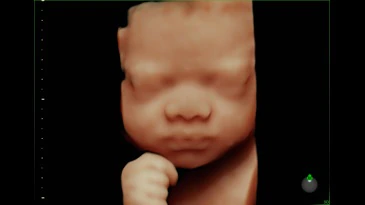

Lo studio del Prof. Susini dispone dell’avanzato sistema ecografico dotato di Intelligenza artificiale completamente integrato che riconosce le 20 visualizzazioni raccomandate dalla International Society of Ultrasound in Obstetrics and Gynecology. Gli strumenti di imaging che sfruttano la potenza dell'intelligenza artificiale consentono di identificare automaticamente ad un livello superiore l'anatomia fetale rispetto a quella visualizzata nelle viste ostetriche standard. Una combinazione di tecniche avanzate di illuminazione e oscuramento della pelle in 3D per visualizzare immagini con chiarezza e profondità senza precedenti e di misurazione della biometria fetale, che consente di allineare e visualizzare correttamente le immagini e le misurazioni consigliate e necessarie per la valutazione del cervello fetale.